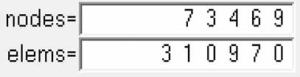

A three-dimensional finite element model of T11–L3 with the screw-rod system was obtained after the screw-rod system was added; it consisted of 310,970 elements and 73,469 nodes (the nodes and elements of T11–L3 Model with Pedicle Screw System Figure 11).